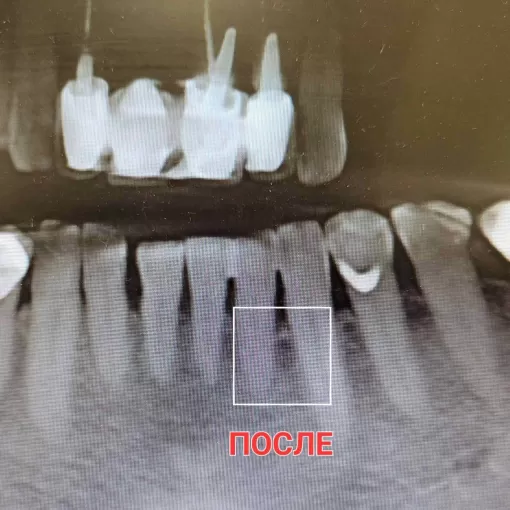

По данным КЛКТ в области зуба 4.6 был выявлен воспалительный очаг. Проведено эндодонтическое лечение с использованием микроскопа, с последующим протезированием коронкой из диоксида циркония.